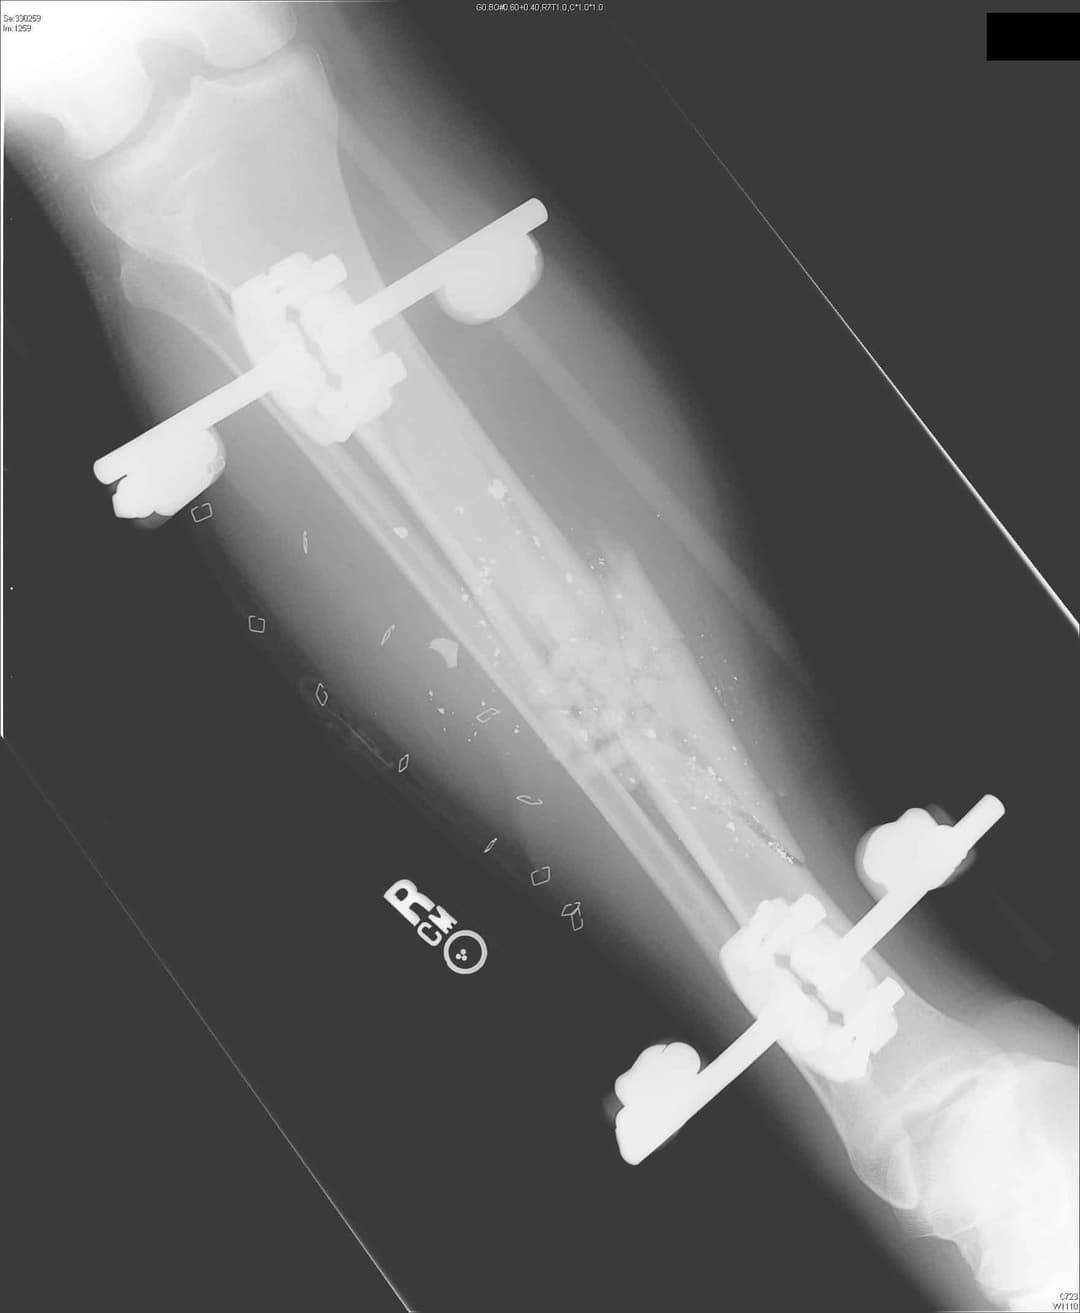

1. див. зобр. 8. Переднезадня рентгенограма встановлення зовнішнього фіксатора з приводу перелому великогомілкової кістки.

Зобр. 8